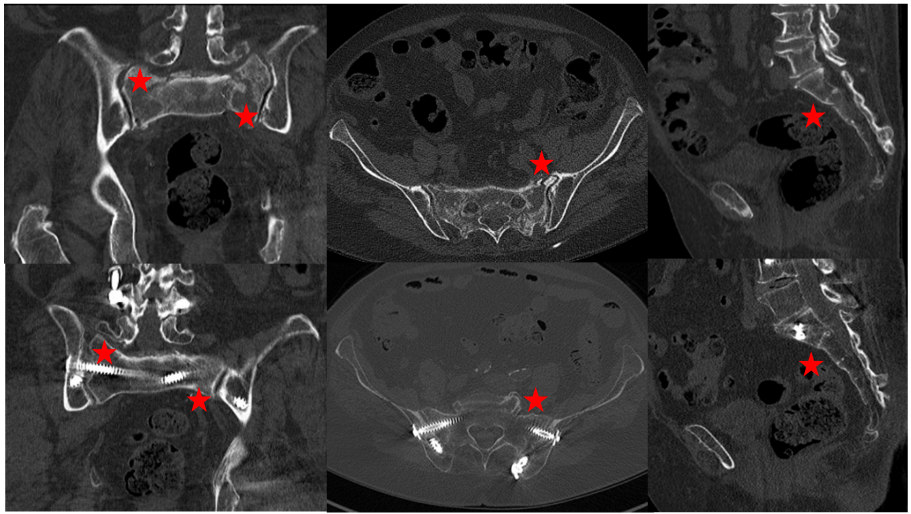

CT evaluation – fracture healing

Criteria for bony fusion were visible fracture lines in the anterior and posterior pelvic ring, sclerosis and callus formation (Figure 7 [Fig. 7]). In 11 of the 13 followed-up patients, no fracture line was visible in the sacrum (84.6%). An H-type fracture was present in 11 patients, a visible callus formation at the second sacral vertebral body (horizontal fracture line) was seen in 7 patients. A callus formation was seen in every case of an anterior pelvic ring fracture. Subsequent and adjacent fractures were not seen in any case. Adjacent segment degeneration was found in one patient (at the level L3/4, asymptomatic).

Figure 7: Top row: FFP4b type fracture. The stars mark the fracture zones. Bottom row: bony fusion after triangular stabilization. The stars mark the former fracture zone. No fracture lines visible.